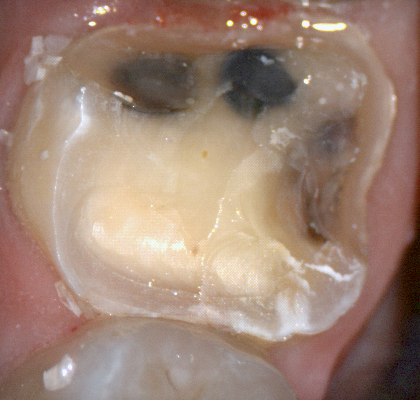

The following pictures depict the sequence of burs we recommend that you use to finish a preparation quickly. While patient is getting numb, take a quick look at the clearance you will need to reach proper material thickness. Once the quadrant is isolated with isolite and optragate, take an occlusal router bur and create a trough to gain the proper depth. Follow that with a flat disk, and you can quickly reduce the occlusal height.

A shoulder bur of .8 mm thickness can help you reduce the interproximal areas as well as the buccal and lingual margin lines. Before finishing the prep, place hemostatic agent like expasyl in the sulcus and place retraction cord. while it is setting, check your reduction. If you need more space, now is the time to reduce some more.